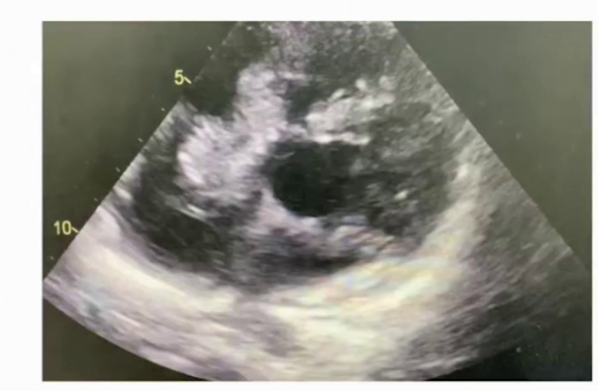

2022.12.19超声提示:室间隔缺损(膜周部);房间隔缺损(继发孔型);三尖瓣反流(重度);心包积液(少量)。

2025.2.23第四次随访超声心动图:三尖瓣赘生物,感染性or非感染性?